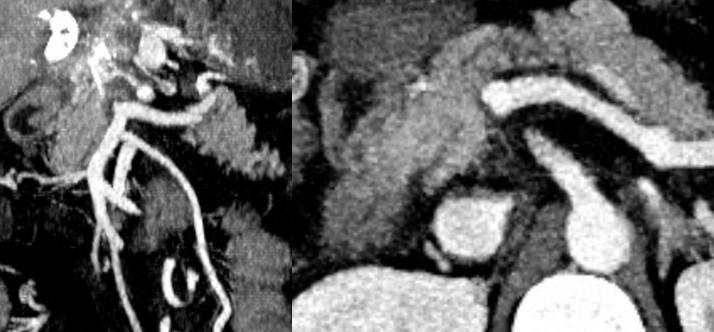

tm nach 11

Hình 2 : Bệnh nhân bị huyết khối hoàn toàn TM cửa